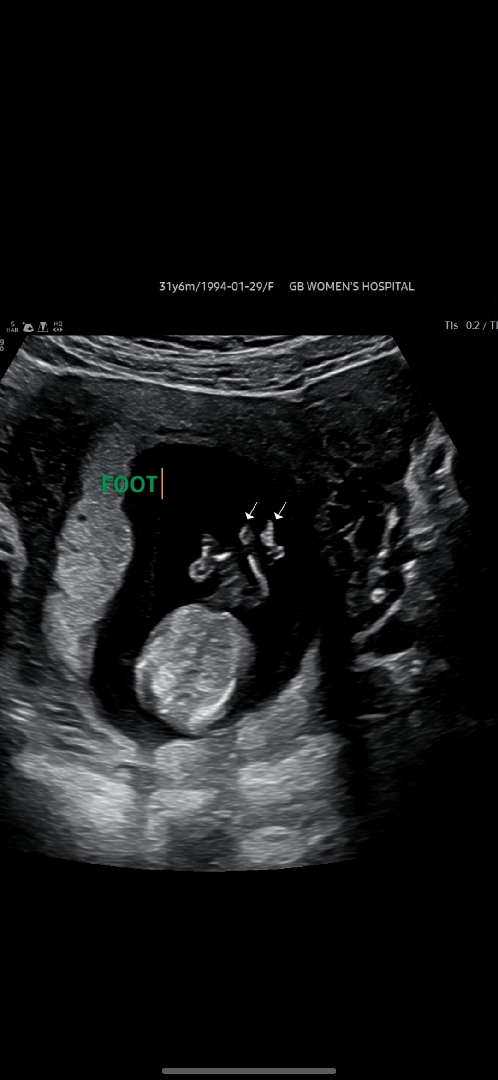

11주6일 초음파성별

지금은 14주4일차인데요! 이 사진으로도 딸인지 아들인지 보일까요??? ㅠㅠ

11주엔 너무 작아서 몰라요 😂 반전가능성도 있구요